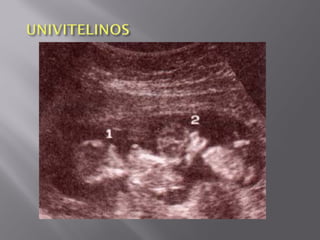

 Gemelos idénticos,univitelinos, uniovulares, son los gemelos provenientes de un óvulo único fecundado por un espermatozoide.  Tienen la misma información genética (genotipo) Son del mismo sexo y las características de las membranas dependen del momento en que se dividen.